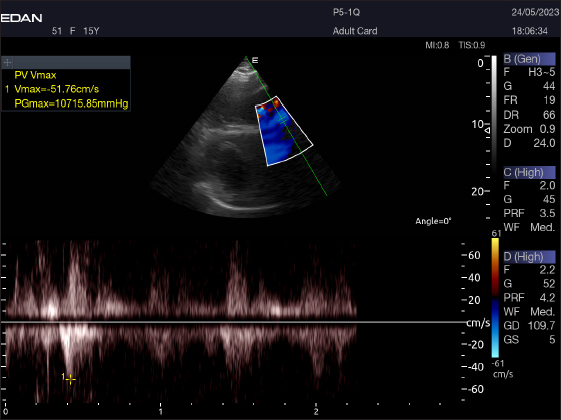

Table 4 provides an overview of pulsed-wave Doppler echocardiographic serial measures in adult racing camels. The pulsed-wave Doppler echocardiographic measurements’ mean values ± standard deviation were recorded for Tv E/A (1.3 ± 0.2 cm2), Mv E/A (1.3 ± 0.2 cm2), Av max (−88.2 ± 25.1 cm/second), and Pv max (−59.2467 ± 17.4 cm/second), as shown in Table 4.

Right parasternal ultrasonography

There was difficulty in measuring the pulmonary valve from the right short parasternal view in most cases (58.4%) (Fig. 7).

Fig. 7. Right parasternal short axis of a 17-year racing she-camel showing pulsed wave Doppler of pulmonary valve.